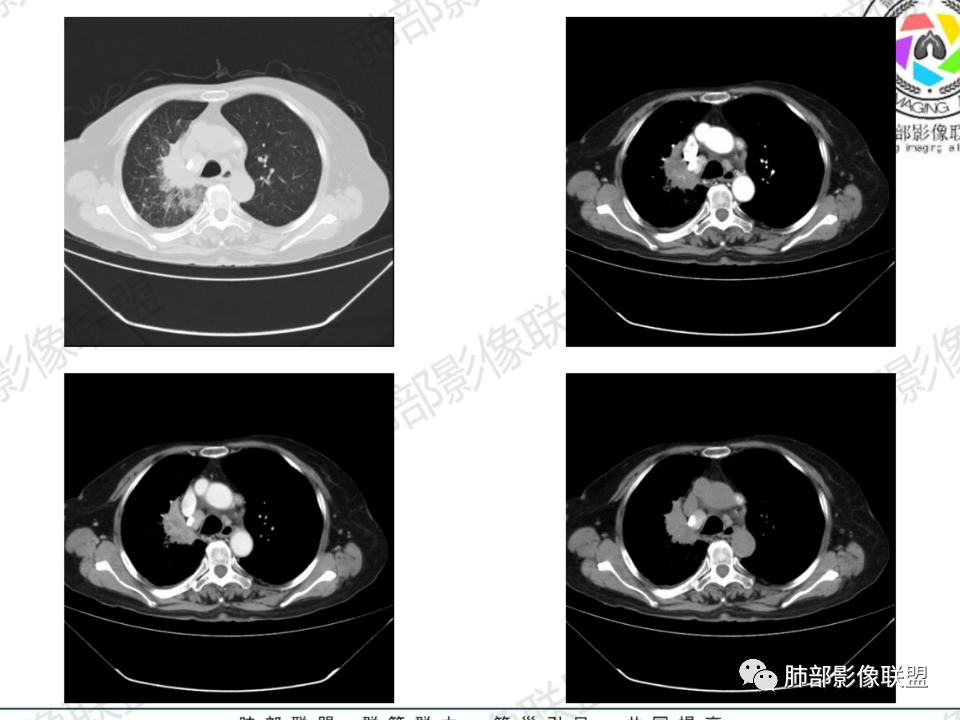

老年患者,病程中等,有咳嗽/喘息/低热症状,肿瘤标志物升高,感染标志物不高,右上肺新生物,中央型,边界清楚,有分叶,支气管截断,内有坏死,不均匀强化,考虑肺癌,鳞癌?

那个人:老年女性,亚急性病程,咳嗽发热。有垂体前叶功能减退,目前激素替代治疗,长期激素,量小,不知道累积量,没有目前激素水平指标。既往有淋巴结结核病史。肿瘤标记物Ca125升高。血沉升高,C反应蛋白轻度异常。影像,右肺上叶靠近肺门团块影,右肺门淋巴结钙化肿大,支气管狭窄,局部增厚,团块影外朝内改变,强化明显,血管破坏不明显,有粘液。和纵隔胸膜分界清楚,周围肺组织有斑片渗出影,右侧胸腔积液,考虑炎性?结核?支气管镜检查除外恶性飞鹰行动:老年患者,影像表现 右肺上叶占位性病变,边界清楚,有分叶征,内见细小钙化,右肺上叶支气管截断,增强病灶不均匀强化,病灶内有条状坏死区(扩张的支气管?),纵膈内未见增大淋巴结,考虑炎性病变,结核可能。一切∮随缘:右肺上叶实性肿块形态不规则,呈三角形,边缘分叶,边界伴有磨玻璃影,近段支气管未见明显显示,可能堵塞,病变平扫密度均匀,增强后可见低密度坏死无强化,周围略强化,右肺下叶散在结节。心包积液,及右侧胸腔积液,临床:有低热,低蛋白血症,肿瘤标记物高,考虑恶性:腺癌,神经内分泌癌(强化偏弱了),淋巴瘤,鉴别:结核红星:老年女性患者右肺上叶,肺门上区 分叶状肿块 ,右肺上叶支气管显示不清,增强扫描肿块,中等程度强化可见小斑片状坏死区,病灶内部可见斑点状钙化灶,病灶周围可见斑片状及小斑点状影,纵膈淋巴结增大,其他区域,胸膜下可见斑点状钙化。考虑肉芽肿性病变,结核的可能性大。老年患者最排除肿瘤性病变腺癌。土娃:右上肺不规则肿块影,边缘分叶,边界磨玻璃影欠清,病灶分叉状,内见点状钙化影及坏死灶,支气管堵塞,病灶增强强化不明显。考虑瘤样结核,鉴别淋巴瘤。张小兵:老年女性,亚急性病程,右肺上叶见不规则肿块,边缘平直凹陷为主,周围GGO边界不清,内见点状钙化及坏死灶,增强持续性渐进强化,右侧少量胸腔积液,双肺门及纵隔肿大淋巴结伴钙化,综合考虑慢性炎症。saf:老年患者,影像表现 右肺上叶占位性病变,边界清楚,有分叶征,增强病灶明显不均匀强化,纵膈内未见增大淋巴结,考虑炎性病变,结核可能。小兜:老年女性,咳嗽喘息一月,发热三天,肿瘤标志物升高,长期激素替代治疗。CT示右肺上叶近肺门不规则实变影,周围伴磨玻璃影,增强持续性渐进强化,内部血管破坏不厉害,内部可见多发条形低密度灶,右侧胸腔可见少量积液,双肺门及纵隔可见钙化淋巴结,考虑为炎性病变,结核可能玫:女,79咳嗽,喘息一月,发热三天入院,右肺上叶不规则形软组织密度肿块影,边界清晰,边缘见分叶及细短毛刺,病灶内见点状钙化影及稍低密度区,病灶边缘呈磨玻璃样改变,增强扫描,病灶呈不均匀性强化,考虑炎性病变,鉴别鳞癌。大雄:老年女性,既往诊断淋巴结结核,提示已治愈,近2年服用激素,诱导结核复燃→发热;纵隔肺门淋巴结肿大钙化,压迫支气管,右肺上中下叶支气管均狭窄→喘息咳嗽;尖段支气管受累闭塞→肺不张、支气管粘液栓;累及胸膜,结核性胸膜炎并胸水→右侧胸痛;实验室,血沉快,CA125高,低蛋白,符合;下一步,支气管镜尖段支气管刷检抗酸染色周太狼:老年女性,亚急性病程,肿瘤标志物升高。CT示右肺上叶尖段不规则肿块影,有分叶、收缩,周围伴磨玻璃影,增强渐进强化,内部可见多发条形低密度灶,右侧胸腔及心包少量积液,纵隔内淋巴结稍增大。倾向于恶性病变,肺癌伴阻塞性炎变可能。丽:老年女性,右肺上叶不规则软组织肿块,边缘清晰,内密度不均,可见点状钙化及粘液栓,周围可见片状高密度影,增强后均匀强化,内多发低密度,纵膈多发钙化淋巴结,考虑结核可能大,建议结合支气管镜检查除外肿瘤宇宙:右胸廓缩小,右肺上叶团块影及不张,平直边,周围磨玻璃影,纤细胸膜牵拉,上叶尖段支气管堵塞,明显延迟强化,可见支气管粘液栓,两肺门钙化淋巴结,右侧胸水,考性炎性肉芽肿,鉴别腺癌王秀仙:右肺上叶肺门区肿块,上叶支气管开口阻塞,形态不规则,密度不均,内可见支气管粘液栓及多发小灶性坏死,周围磨玻璃影边缘模糊,渐进强化,右侧胸腔积液、胸膜钙化,考虑炎性肉芽肿性病变,慢性炎症。鉴别鳞癌,结核。刘丹:老年女性,右肺上叶肿块伴钙化,右肺上叶支气管截断,增强后均匀强化,周边可见点片状模糊影,右侧胸腔积液,右肺门淋巴结增大,考虑占位并阻塞性炎症,肿瘤?结核?建议纤支镜检查。小飞:右肺上叶纵隔旁软组织肿块,边缘深分叶、长毛刺及毛刷样短毛刺,边缘磨玻璃影,磨玻璃边界模糊,支气管截断,平扫密度不均,可见点状钙化,增强不均匀明显强化,心影增大,心包积液,右侧胸腔积液,考虑恶性肿瘤,腺癌?秦化君:右肺上叶不规则分叶软组织密度肿块,边缘清晰,胸膜牵拉,周围花花草草,上叶尖段支气管阻塞,内可见点状钙化,增强后密度不均可见支气管粘液栓及坏死区,内见血管分枝。中间段及中叶,下叶支气管狭窄,壁见钙化。右肺门淋巴结肿大,右侧胸腔积液,心包粘连肥厚。考虑1右上肺恶性病变,鳞癌?2右肺多叶段支气管狭窄,考虑支气管内膜结核?3胸腔积液及肺门淋巴结肿大,转移?风儿:老年女性,右肺上叶肿块,形态不规则,外围大内带小,边缘分叶膨隆平直及毛糙,密度不均,内见支气管粘液栓及多发小灶性坏死,坏死边缘清晰 ,渐进强化,上叶尖段支气管阻塞,叶支气管壁有局限性增厚,邻近胸膜腔微积液;纵隔及双肺门淋巴结肿大,部分钙化,右侧胸腔积液、心包积液、胸膜钙化,考虑炎性,肉芽肿性结核可能性大。鉴别鳞癌,女性及血供均不支持;腺癌,坏死边界太清晰。流心明智:老年女性,79岁,咳嗽、气短1月,发热3天。胸CT:右肺上叶见不规则肿块,边缘有膨隆、有平直凹陷,周围GGO边界不清,病灶内见点状钙化、粘液栓,尖段支气管未见,增强持续性渐进强化,右侧少量胸腔积液,双肺门及纵隔肿大淋巴结伴钙化,肺动脉增粗。考虑:右上叶尖段堵塞并慢性炎症,支气管TB并结石?鉴别Ca

临床信息:老年女性,亚急性病程,咳嗽发热。有激素使用史。既往有淋巴结结核病史。肿瘤标记物Ca125升高。血沉升高,C反应蛋白轻度异常。 影像所见:右侧胸廓相对狭小,右肺上叶不规则团块影贴附纵隔旁,轻度分叶,整体密度较均匀,偶见钙点。

相应上叶尖端及前段支气管开口未能追踪(阻塞),开口处见钙化。病灶渐进性强化,并衬托出较完整尖段及前段含液支气管影。支气管开口区域未见异常高密度强化(如类癌等)及相对乏血供区(如鳞癌)。病灶区未见液化坏死。右上纵隔及胸廓入口区未见病灶胸膜外突破(栽赃)。

右肺上叶后段等区域散在片状影,边界不清(提示渗出性病灶)。

纵隔及双肺门见钙化淋巴结。心包积液,右侧胸腔积液(提示存在活动新病灶)。双侧胸膜下见多发斑点状钙化,胸廓变形(提示存在结核基础病变可能)。 诊断意见:综上,右肺上叶块状影更符合继发性肺结核。 最后小结:既往诊断淋巴结结核,提示已治愈。近2年服用激素,可疑诱导结核复燃,也可引起发热。纵隔肺门淋巴结肿大钙化,压迫支气管,右肺上中下叶支气管均狭窄,所以引起喘息咳嗽。尖段支气管受累闭塞,导致肺不张、支气管粘液栓,出现条状无强化区。病变累及胸膜,导致结核性胸膜炎并胸水,引起右侧胸痛。实验室检查血沉快,CA125高,低蛋白,均符合结核。下一步,建议支气管镜尖段支气管刷检并抗酸染色。(本段摘自於雄老师精彩发言)